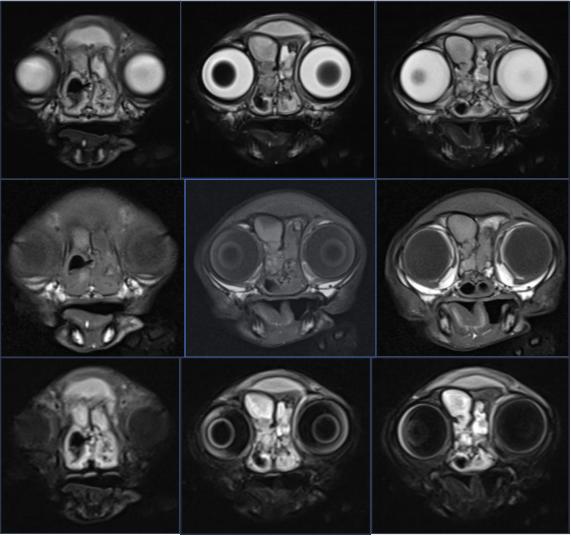

核磁↓↓

核磁结果显示:双侧鼻腔、额窦及额前部皮下可见T1WI等信号、T2WI高信号内容物;双侧局灶

性鼻甲纹理缺失,右侧鼻腔较明显,且右侧鼻骨局灶性溶解;左侧额骨增厚,额窦腔隙较小;腹侧筛板影像不清,双侧嗅球部脑膜T2WI信号增强。小脑尾侧部分实质突入枕骨大孔。双侧鼓室呈T1WI、T2WI低信号,鼓泡壁平滑。